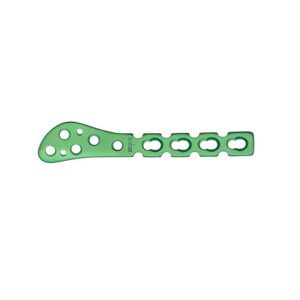

SET DE PLACAS PARA RADIO DISTAL

Conjunto de cuatro placas anatómicas de bloqueo para la fijación quirúrgica de fracturas del radio distal, con opciones volares, dorsales y extendidas para adaptación precisa y estabilidad óptima según el patrón de fractura.